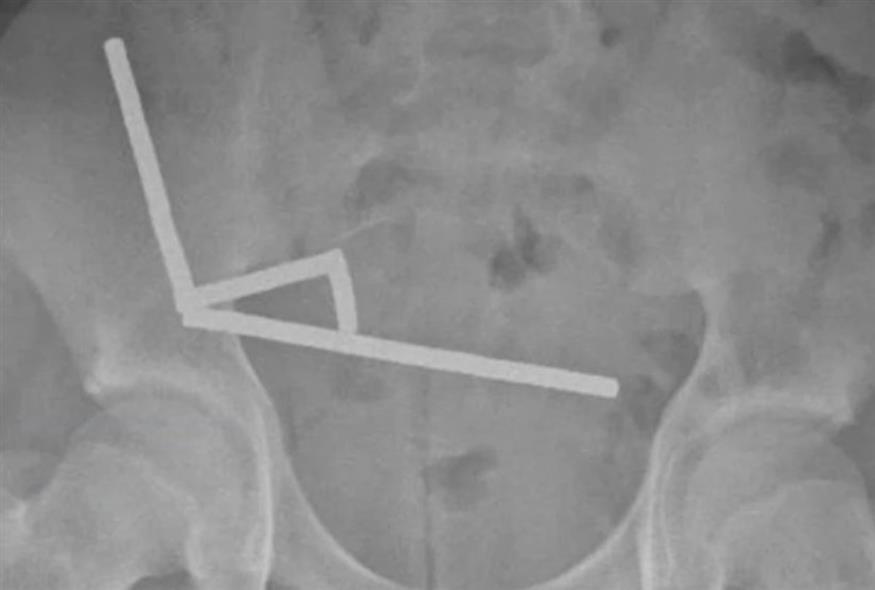

Αφορμή αποτελεί ένα σοβαρό περιστατικό στη Νέα Ζηλανδία όπου 13χρονος κατάπιε σχεδόν 200 μαγνήτες και εισήχθη στο νοσοκομείο με πολύ έντονους κοιλιακούς πόνους.

Όπως αναφέρει το New Zealand Medical Journal, οι μαγνήτες ενώθηκαν μεταξύ τους σε μια περιοχή που ενώνει το λεπτό και το παχύ έντερο και έγιναν αιτία να νεκρώσουν ιστοί λόγω έλλειψης αιμάτωσης. Ο 13χρονος υπεβλήθη σε επέμβαση και παρότι αναρρώνει καλά, έχασε μέρος του εντέρου του.